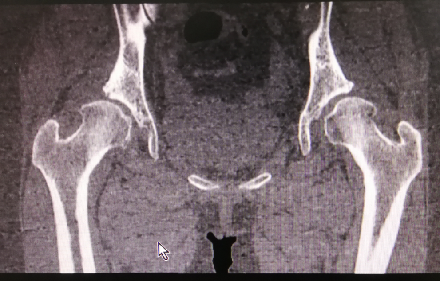

术前X线及髋关节CT图像显示,双侧髋臼明显发育不良,髋臼变浅,右侧髋臼骨质密度不均匀,双侧髋臼对股骨头的包容不足。